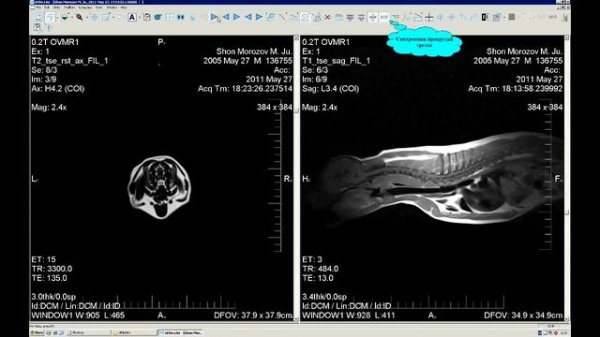

Работаем с eFilm Lite_